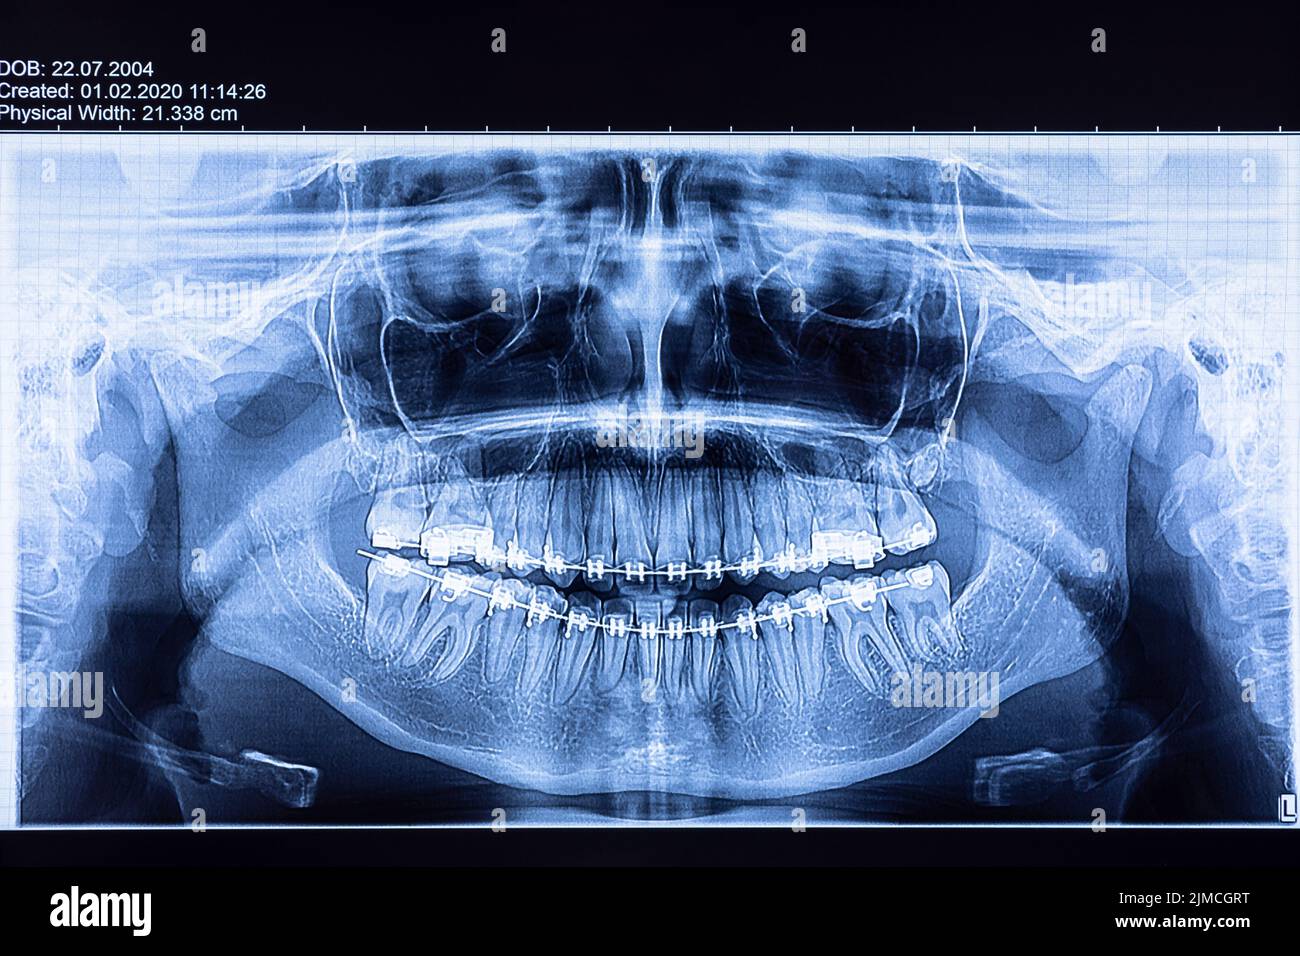

From www.alamy.com

Dental radiography with braces Stock Photo Alamy Define Dental Radiography Radiographs are an important diagnostic tool that supplement our clinical findings. Radiographs are the foundation of imaging diagnostics in dentistry as the main areas of interest in this field are hard tissues of teeth. Think of it as a superpower for dentists. We need to understand how they work. • identify the range of kilovoltage and milliamperage required for dental. Define Dental Radiography.